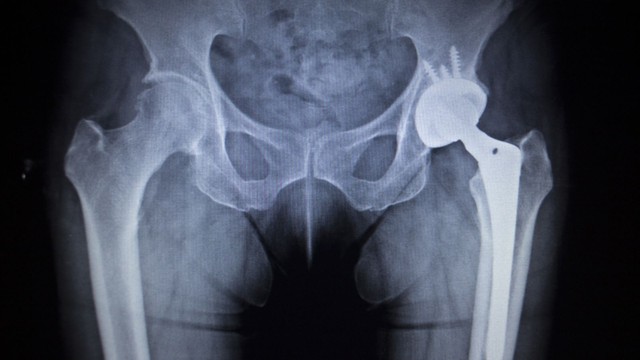

Hoại tử